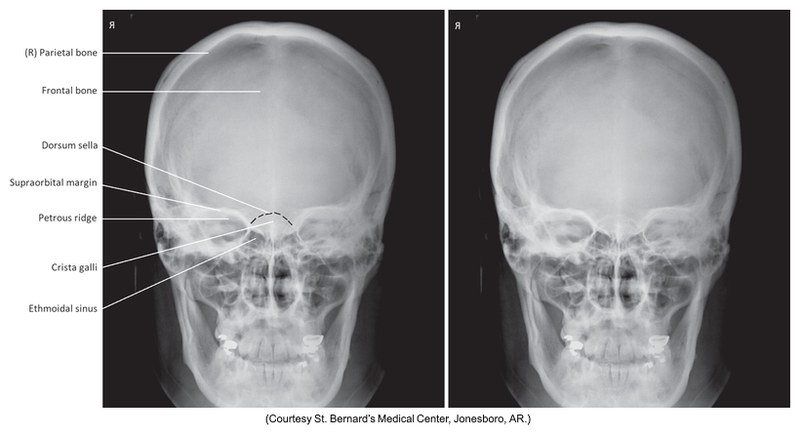

PA projection of skull

PA of skull